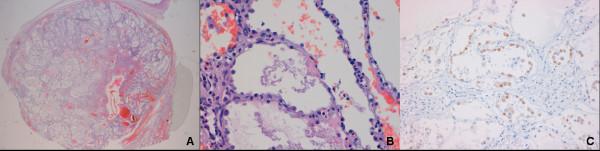

The authors report a clinical case of alveolar adenoma presenting as a solitary pulmonary nodule which was positive to PET and deeply located in the lung. Few cases of alveolar adenomas have been reported in literature; these lesions are considered pulmonary neoplasms with benign behaviour, usually presenting as a peripheral or subpleural coin lesion; the PET activities of such neoplasms were unknown.The present clinical case was singular for the deep location of the nodule and its tight adhesion to left inferior pulmonary vein requiring a lobectomy. In addition, alveolar adenoma PET behaviour has been reported as light positivity.